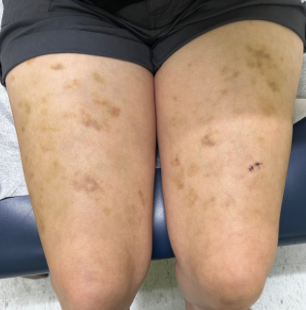

CLINICAL HISTORY: A 30-year-old Latin American female with a medical history of anxiety, hypotension, hypothyroidism, fibromyalgia, and arrhythmias presented to our clinic with episodic spontaneous bruising on both thighs, which had been occurring since February 2022. She reported pain upon palpation but did not have any other systemic symptoms. The patient denied any new medications or recent traumatic events. Her only surgical history included the placement of a cardiac loop recorder two years prior. She had no history of smoking, alcohol use, or illicit drug use. She denied any family history of bleeding or thrombotic disorders, skin cancer, or liver disease. Current medications included midodrine, fludrocortisone, levothyroxine, and diclofenac, and there were no known drug allergies.

Physical examination revealed painful, non-palpable and ecchymotic healing lesions over the anterior aspect of both thighs.